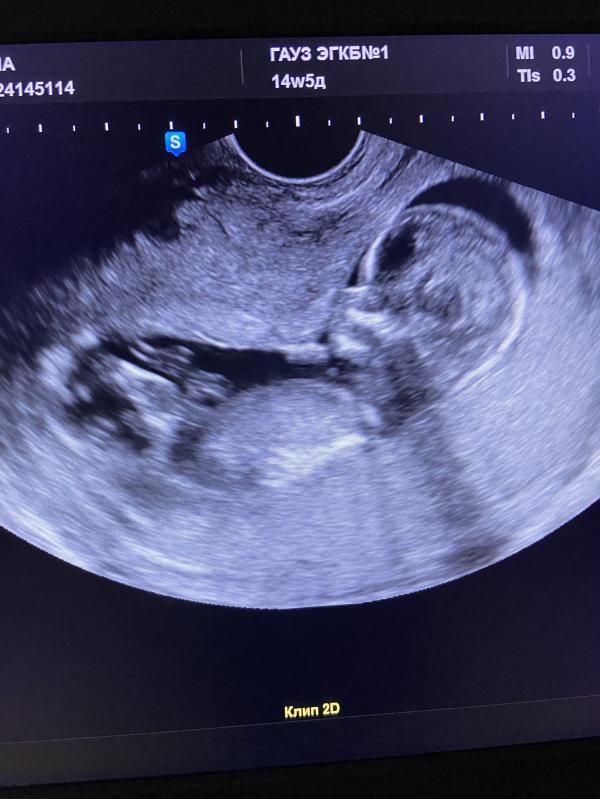

Первый скрининг: все хорошо! Развитие в норме, сердце бьется, анализы ждем, ура!

Сегодня был первый скрининг🥳 Как же я переживала!!!

Итог такой: развитие в норме, сердце бьется, врожденных пороков нет.

Теперь ждём анализы крови🙏

Расти здоровый, мой малыш🤍